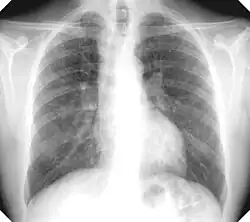

There are three key elements to the diagnosis of silicosis. First, the patient history should reveal exposure to sufficient silica dust to cause this illness. Second, chest imaging (usually chest x-ray) that reveals findings consistent with silicosis. Third, there are no underlying illnesses that are more likely to be causing the abnormalities. Physical examination is usually unremarkable unless there is complicated disease. The examination findings are not specific for silicosis.[20]

For uncomplicated silicosis, chest x-ray will confirm the presence of small (< 10 mm) nodules in the lungs, especially in the upper lung zones. Using the ILO classification system, these are of profusion 1/0 or greater and shape/size "p", "q", or "r". Lung zone involvement and profusion increases with disease progression. In advanced cases of silicosis, large opacity (> 1 cm) occurs from coalescence of small opacities, particularly in the upper lung zones.

With retraction of the lung tissue, there is compensatory emphysema. Enlargement of the hilum is common with chronic and accelerated silicosis. In about 5–10% of cases, the nodes will calcify circumferentially, producing so-called "eggshell" calcification. This finding is not pathognomonic (diagnostic) of silicosis. In some cases, the pulmonary nodules may also become calcified.

Chronic simple silicosis

Usually resulting from long-term exposure (10 years or more) to relatively low concentrations of silica dust and usually appearing 10–30 years after first exposure.[23] This is the most common type of silicosis. Patients with this type of silicosis, especially early on, may not have obvious signs or symptoms of disease, but abnormalities may be detected by x-ray. Chronic cough and exertional dyspnea (shortness of breath) are common findings. Radiographically, chronic simple silicosis reveals a profusion of small (<10 mm in diameter) opacities, typically rounded, and predominating in the upper lung zones.